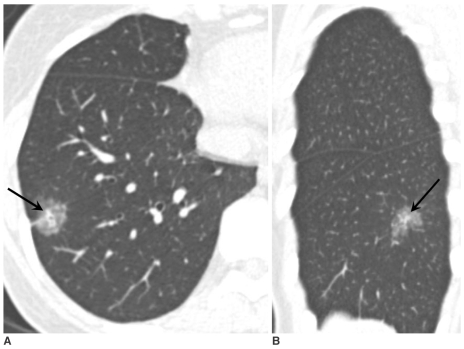

肺結(jié)節(jié)是指肺內(nèi)直徑小于或等于3 cm的類圓形或不規(guī)則形病灶,影像學(xué)表現(xiàn)為密度增高的陰影,可單發(fā)或多發(fā),邊界清晰或不清晰的病灶。

依據(jù)結(jié)節(jié)密度將肺結(jié)節(jié)分為三類:實(shí)性結(jié)節(jié)、部分實(shí)性結(jié)節(jié)和磨玻璃密度結(jié)節(jié)。不同密度的肺結(jié)節(jié),其惡性概率也不同。其中,部分實(shí)性結(jié)節(jié)的惡性概率較高,依次為磨玻璃密度結(jié)節(jié)及實(shí)性結(jié)節(jié)。

而肺結(jié)節(jié)也有“良”有“惡”。以磨玻璃結(jié)節(jié)為例,導(dǎo)致其出現(xiàn)的病因很多,可能是良性的局限性炎癥、局限性肺纖維化等;可能是病理學(xué)上較為良性的不典型腺瘤樣增生;可能是原位腺癌;也可能是惡性的浸潤(rùn)性腺癌。

2.良性結(jié)節(jié)邊界完整;惡性結(jié)節(jié)形態(tài)不規(guī)則,比如有分葉、毛刺、胸膜牽拉、含氣細(xì)支氣管征和小泡征、偏心厚壁空洞等;